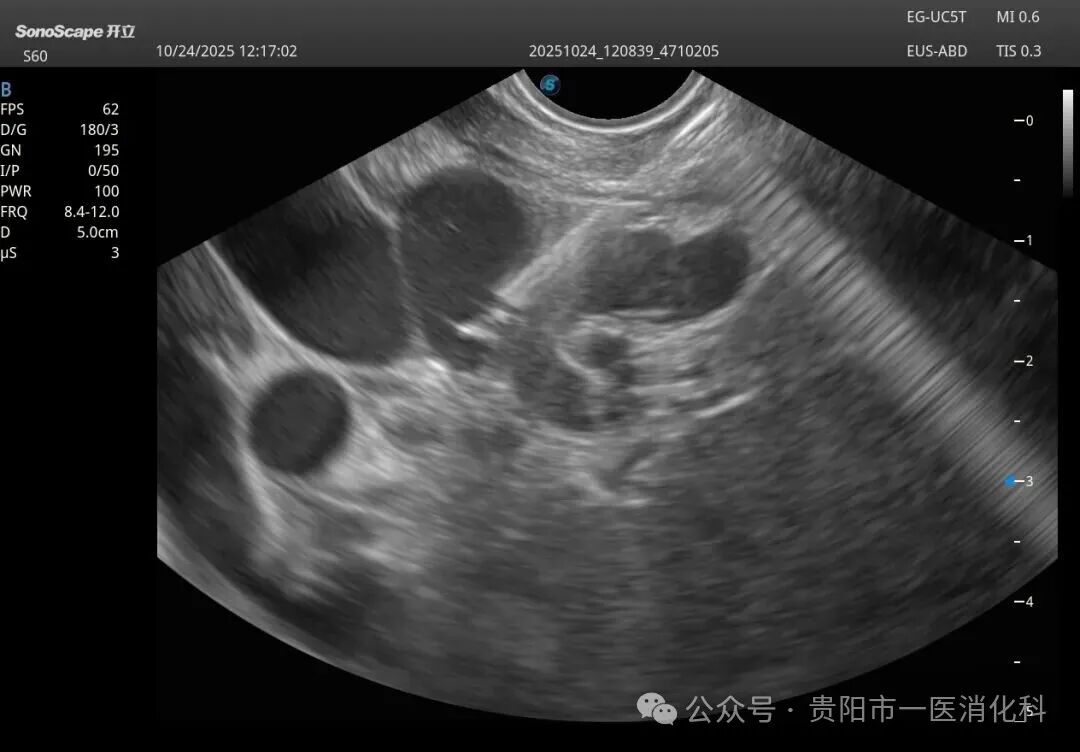

在王俊雄教授的全程指导下,手术如期进行。术中,专家团队首先将超声内镜送达胃底,屏幕上立即清晰显示出曲张静脉的横断面、深度、血流以及其来源血管。在超声的“火眼金睛”引导下,穿刺针犹如被安装了“GPS导航”,精准刺入目标血管。随后,医生们先将数个微弹簧圈送入血管内,构建一个坚实的“巢”,再注入医用组织胶水。弹簧圈与组织胶迅速结合,形成稳固的复合栓塞物,彻底封堵了致命的曲张静脉。整个手术过程流畅,术后患者生命体征平稳,安返病房。

2.安全稳固:先放弹簧圈再注胶,形成了“钢筋+混凝土”般的稳固结构,既避免了胶水被血流冲走导致异位栓塞的风险,又显著降低了术后再出血率。